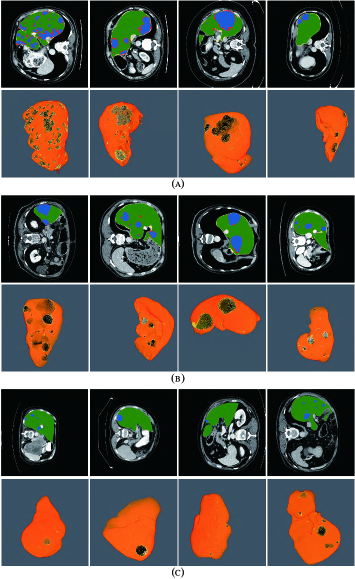

Refer to caption

Figure 10: Automatic liver and tumor segmentation with RA-UNet. The green regions indicate the correctly extracted liver, the yellow regions are the wrongly extracted liver, the blue color depicts the correctly extracted tumor regions and the red color means wrongly extracted tumor. The first row of each subplot shows four slices from different volumes in the axial view and the second row of each subplot shows the corresponding 3D view of the entire liver/tumor segmentation results. (a) is from the LiTS dataset. (b) is from the 3DIRCADb dataset. (c) shows the segmentation results on the LiTS test datasets. Note that no ground truth is provided for the LiTS test dataset.

Fig. 10 shows the liver/tumor segmentation results. It shows that liver regions which are large in size are successfully segmented and tumors that are tiny and hard to detect can be identified by the proposed method as well. Due to the low contrast with the surrounding livers and the extremely small size of some tumors, the proposed method still has some false positives and false negatives for tumor extraction.